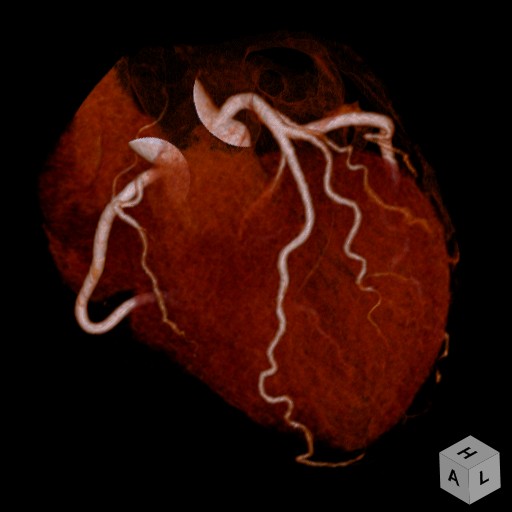

写真 VR画像

VR画像:立体的に観察することができます。